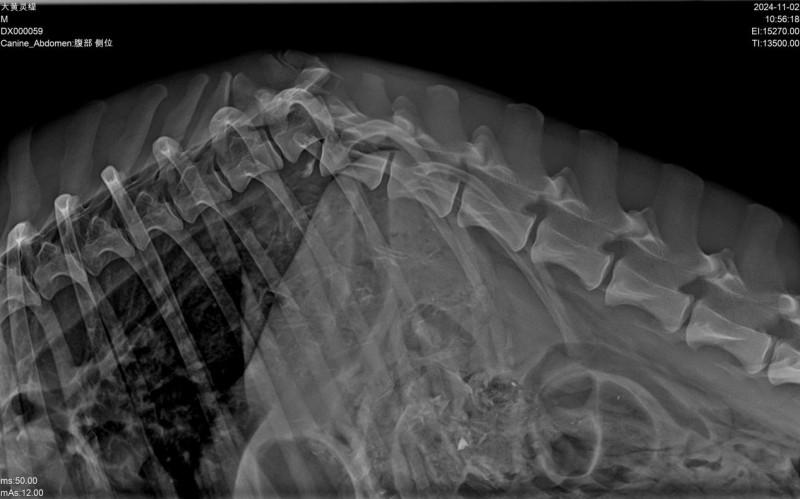

优势1:超强穿透,全体型宠物全覆盖,杜绝重复拍摄宠物诊疗中,“穿透不足”是大型宠、肥胖宠物成像的核心痛点——常规低压DR拍摄大型犬腰椎、骨盆等厚实部位时,射线难以穿透深层组织,导致图像模糊、骨骼轮廓不清,不得不反复镇静、重复拍摄,既耗时费力,又增加宠物应激反应与辐射累积风险。

必康32kW高压发生器可稳定输出高强度、高均匀度的X射线,凭借超强穿透能力,轻松适配全场景宠物体型需求:无论是藏獒、阿拉斯加等大型犬的厚实骨骼与肌肉组织,还是肥胖宠物的深层脏器,都能一次性穿透,精准捕捉病灶细节;针对猫咪、小型犬、鹦鹉等小型异宠,设备可精准调控射线能量,避免成像过曝,兼顾穿透性与细节捕捉力,真正实现“一次拍摄、一次成像合格”,大幅降低重复拍摄率,为宠医减负、为宠物护航。